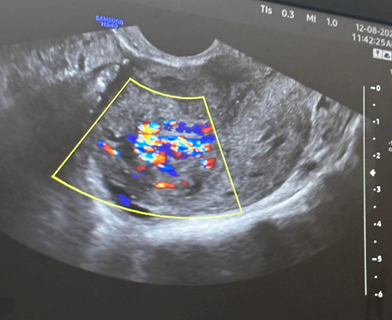

To be double sure, we tested her beta HCG level which was 36.7 mIU/ml. We performed a pelvic angiogram for better visualization. It showed hypertrophied bilateral uterine arteries and intrauterine spiral arteries with prominent uterine blush, bilateral external iliac arteries and infrarenal abdominal aortogram was normal. In view of these findings, uterine artery embolization was decided upon.

All routine pre-procedure workup was done wherein the patient was found to be severely anaemic with a hemoglobin level of 6.2 g/dL. All of her other investigations were within normal limits. Two bags of packed cells were transfused to optimize the hemoglobin to 9.6 g/dL and she was taken up for the embolization with right femoral access. Uterine artery embolization (UAE) has been proven to be a highly successful treatment modality for AVM due to the non-invasive and quick resolution of symptoms.

Furthermore, it avoids the associated complications of operative interventions like hysterectomy. Super selective catheterization on the right femoral artery was done using Progreat™ micro catheter and embolization was carried out using polyvinyl (PVA) 150-250 microns particles. Postprocedural angiogram revealed near total (99%) reduction in vascularity of mass lesion. Post procedure recovery of the patient was uneventful. Her bleeding had stopped completely and she was discharged after one full day of observation post the procedure.

The patient was asked to follow up one week after the procedure wherein she had no complaints at all and had recovered completely. Presently, she has been called for monthly follow-up on long term basis (Figure 2&3).

Figure 2 Pre-embolization DSA showing vascular supply.

Figure 3 Postembolisation DSA showing reduced vascularity (upto 99%).